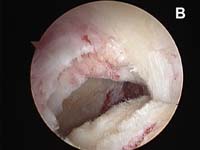

- the rotator cuff tear is identified and loose, degenerated, and frayed tissue around the cuff edge must be removed back to healthy tissue. This process is called débridement.

- The edge of the cuff tear must be brought back to its normal position without undue tension. This process is accomplished using techniques called mobilization or in larger tears, a technique called margin convergence. (See Fig. 4).

- The tear must be fixed into place using specially-designed suture anchors that allow the surgeon to approximate the cuff tear securely to the bone.